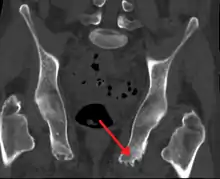

Enthesopathy of the pelvis likely due to ankylosing spondylitis